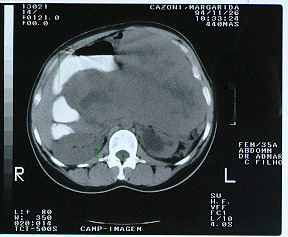

No pós-operatório foi submetida a radioterapia adjuvante no retroperitôneo. Evoluiu bem, sem evidência de recidiva durante o segmento ambulatorial até setembro de 1996, quando o ultrassom abdominal mostrou metástase hepática isolada (imagem 3), confirmada pela Tomografia computadorizada.

Foi submetida a nova laparotomia com ressecção da metástase de 3,5 x 4 cm, localizada entre os segmentos 5 e 6 hepáticos. O AP confirmou o diagnóstico de leiomiossarcoma metastático com margens livres.